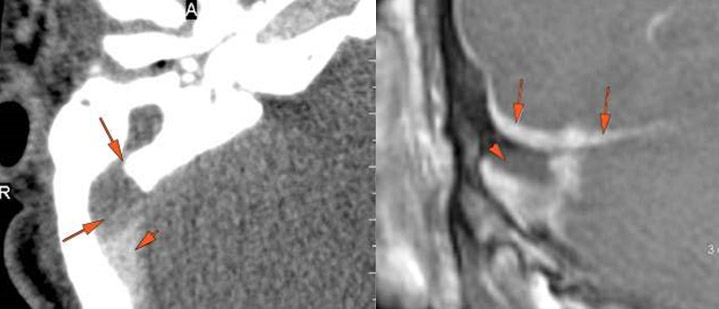

There is dural reactive changesubperiosteal, epidural or subdural abscess long the roof of the mastoid or middle ear or the surfaces of the petrous portion of the temporal bone.

There is dural reactive changesubperiosteal, epidural or subdural abscess along the roof of the mastoid or middle ear or the surfaces of the petrous portion of the temporal bone.

There is gas in the subarachnoid space or otherwise intracranial.

There is dural reactive change along the floor of the middle cranial fossa or along the inner surfaces of the petrous portion of the temporal bone.

There is a subperiosteal, subdural or epidural abscess along the floor of the middle cranial fossa or along the inner surfaces of the petrous portion of the temporal bone.

There is likely meningitis involving the inferior temporal lobe or adjacent cerebellum

There is likely cerebritis involving the inferior temporal lobe or adjacent cerebellum.

There is brain edema and/or evolving abscess present or, specifically, involving the inferior temporal lobe or adjacent cerebellum.